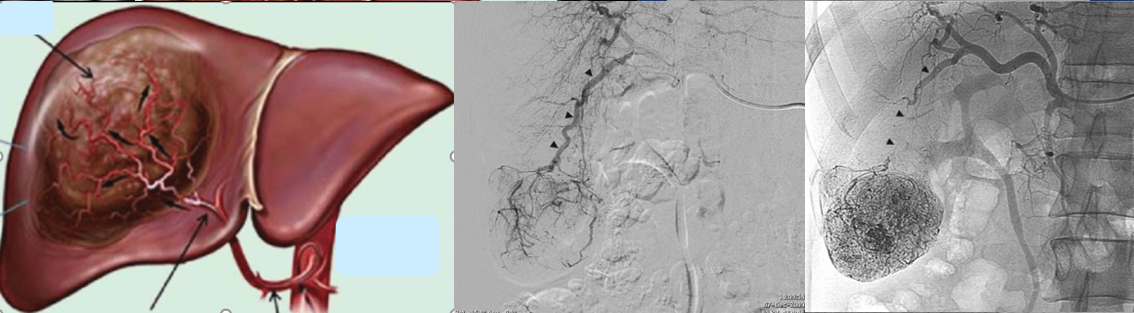

Hình 1: Hình ảnh khối u trong gan